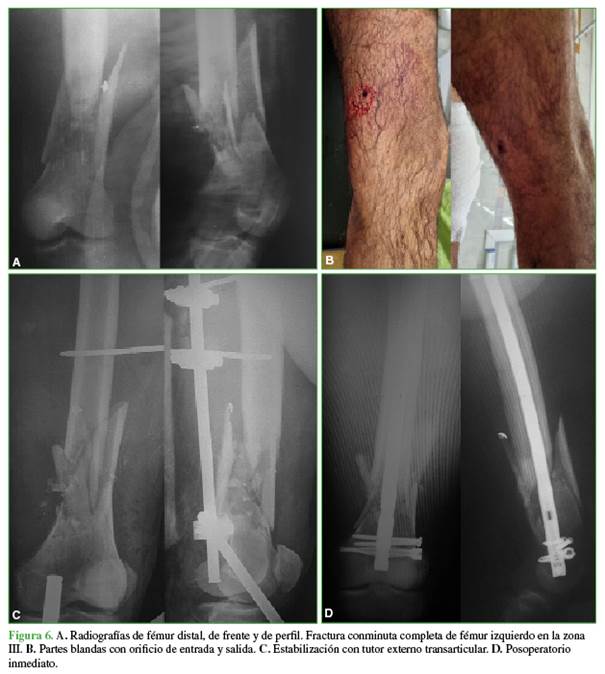

Los métodos de fijación utilizados se distribuyeron de la siguiente forma: 19 (54,29%) con clavo endomedular (Figuras 6 y 7) y siete (20%) que comprometían a la zona III con placas anatómicas bloqueadas.

Las fracturas incompletas del tercio medio pueden tratarse de forma incruenta con un período de carga limitada.18 Los tres pacientes de nuestra serie fueron tratados mediante inmovilización con yeso cruropedio y descarga de peso. Todas las fracturas completas de la zona II fueron tratadas con reducción y osteosíntesis con enclavado endomedular acerrojado.

En la actualidad, el clavo endomedular retrógrado o anterógrado es el método de elección para la resolución de las fracturas de fémur por arma de fuego.19 En una revisión sistemática, se halló una tasa global del 0,18% de artritis séptica de rodilla posterior a la fijación con clavo endomedular retrógrado.20 El único caso con esta complicación fue un paciente con fractura supracondílea tratado con clavo endomedular retrógrado.